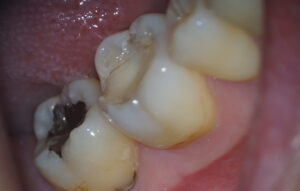

治療前

しみる歯をマイクロスコープで確認すると…

つめものが欠けているところが数カ所あり、これがしみる原因と考えられます。

歯の量が少なく、亀裂が入ってしまっているところも・・・

青丸:詰め物の欠け 赤丸:亀裂